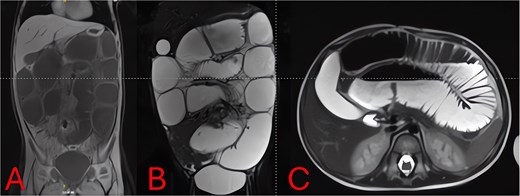

On hospital Day 2, an abdominal MRI without contrast confirmed marked fluid-filled small-bowel loop dilation and a focal transition point in the right lower quadrant (Fig. 3A). Axial sequences demonstrated a periappendiceal fluid collection with mesenteric edema and a possible appendicolith (Fig. 3B). A sagittal plane showed the abscess tracking into the pelvis (Fig. 3C), indicating perforated appendicitis causing adhesive small-bowel obstruction.

MRI of the abdomen—identification of obstruction cause. (A) Coronal T2-weighted MRI showing multiple fluid-filled, dilated small-bowel loops and a focal right lower quadrant transition point. (B) Axial T2-weighted MRI demonstrating a periappendiceal abscess with mesenteric edema compressing adjacent ileal loops. (C) Sagittal MRI view highlighting appendiceal abscess boundaries and a possible appendicolith.